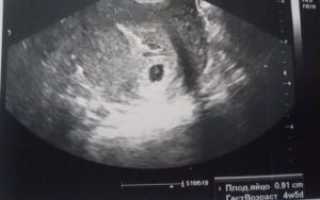

Плодное яйцо можно увидеть начиная с 3 недели. Оно представляет собой образование темного цвета, круглой формы, окруженное тонкой оболочкой, до 5 мм в диаметре. Сам эмбрион в этот период с помощью УЗИ увидеть нельзя, он слишком маленький. Различимым на экране он становится в начале 2 месяца. Это объект продолговатой формы, который закрепляется в плодном яйце при помощи пуповины.

Увидеть беременность на УЗИ можно уже с трех – четырех недель, когда плодное яйцо достигает трех миллиметров приблизительно. Далее с появлением и ростом эмбриона размеры его увеличиваются.

В пять недель – это семь миллиметров, а в восемь – двадцать семь и более миллиметров.

В начале четвертой недели наступает то время, когда видно плодное яйцо на УЗИ. Правда, оно имеет совсем небольшой размер, всего 1 мм диаметром, зато обладает огромным потенциалом. При таком размере рассмотреть, как происходит развитие будущего ребеночка, никак нельзя, потому что размер эмбриона слишком мал.

Следующее обследование проводят через три недели после первичного. За этот срок происходят интересные метаморфозы с плодным яйцом. Если в начале четвертой недели оно было диаметром 1 мм, то уже через два дня утроит размер. К концу недели диаметр оболочки достигнет 5 мм, а у эмбриона начнут закладываться:

Сам эмбриончик будет длиной 1 мм.

Если УЗИ показало, что размер плодного яйца 7 мм, определить, какой это срок, несложно. Учитывая, что к первому дню 5-й недели оно вырастает до 6 мм, скорее всего, это будет середина пятой акушерской недели.